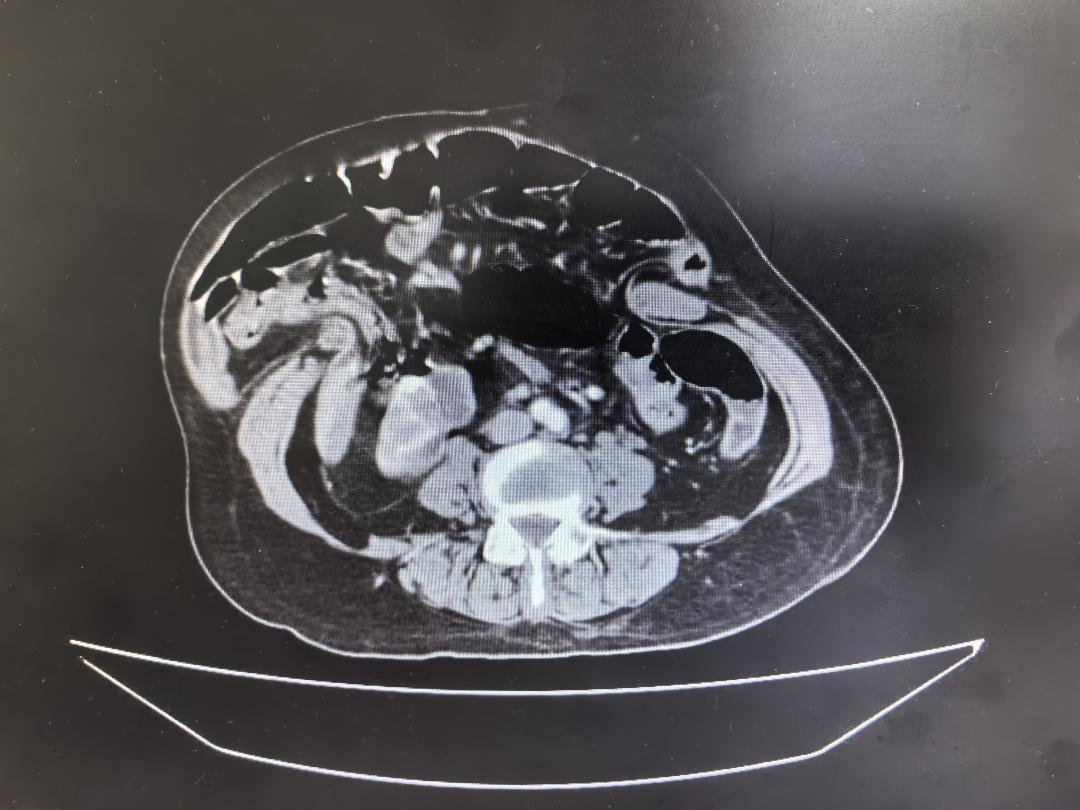

此前,张阿姨曾在当地医院接受过疝修补手术,然而手术未能成功,病情非但没有好转,反而愈发严重。随着时间的推移,腹部切口处的“肿物”不断增大,腹壁缺损长度竟达31厘米之巨,两侧腹直肌分离最宽处更是达到15厘米,整个腹部形同一个被暴力撕开的口袋,模样骇人。

此次入院后的检查结果显示,张阿姨不仅腹部病情复杂棘手,全身状况也十分堪忧。她同时合并低钾血症、甲状腺功能减退、慢性肾功能不全(肌酐高达384μmol/L)以及贫血(血红蛋白仅76g/L)等多种基础疾病,身体犹如一座摇摇欲坠的危楼,随时可能崩塌。

在艰难分离粘连后,又一个难题接踵而至。术中,医生将右半结肠及约60cm小肠一并切除,然而,当尝试将小肠及胃等组织还纳至腹腔时,却发现腹腔根本无法关闭。原来,患者双侧腹肌分离距离过宽,就像两扇无法合拢的大门,直接缝合已无可能。此时,麻醉医生迅速调整麻醉方案,给予患者最充分的肌松,为手术争取宝贵空间。郑燕生当机立断采取腹直肌前鞘翻转术重塑腹壁结构,同时运用腹横肌分离技术(TAR)扩大腹腔容积,经过一番紧张而细致的操作,终于成功将腹壁完全关闭,并进行了腹壁补片修复。